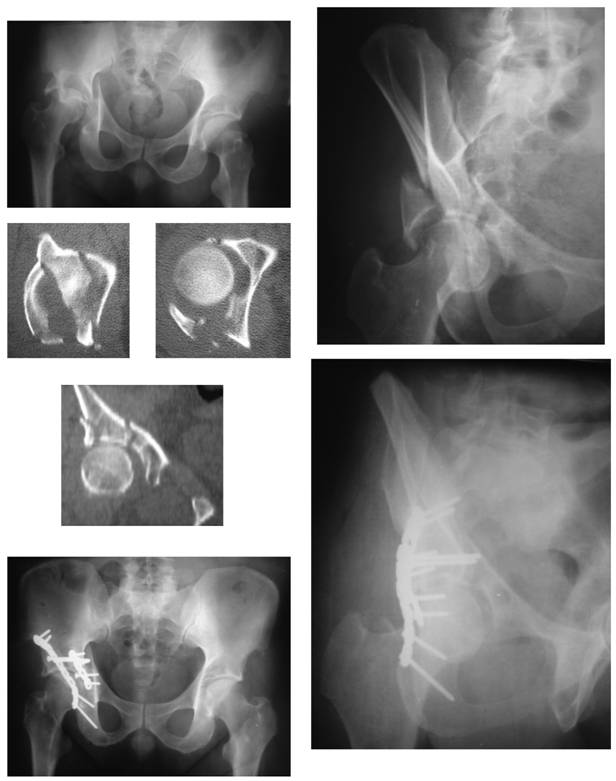

Figure 1

Pre-operative radiographs and CT scan, and postoperative radiographs of a patient (31 y/o female, road-traffic accident, unrestrained) who had fixation of the anterior component of the transverse acetabular fracture with an extra-long small fragment cortical screw ('home-run screw'). Note that the long screw bends as a result of the intimate contact with the pelvic brim. Follow-up duration of 18 months.